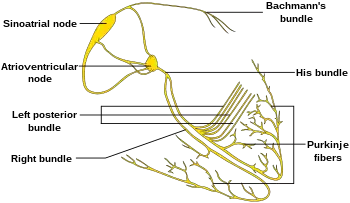

Electrical activity in the normal human heart begins when a cardiac action potential arises in the sinoatrial (SA) node, which is located in the right atrium. From there, the electrical stimulus is transmitted via internodal pathways to the atrioventricular (AV) node. After a brief delay at the AV node, the stimulus travels through the bundle of His to the left and right bundle branches and then to the Purkinje fibers and the endocardium at the apex of the heart, then finally to the ventricular myocardium.

The AV node serves an important function as a "gatekeeper", limiting the electrical activity that reaches the ventricles. In situations where the atria generate excessively rapid electrical activity (such as atrial fibrillation or atrial flutter), the AV node limits the number of signals conducted to the ventricles. For example, if the atria are electrically activated at 300 beats per minute, half those electrical impulses may be blocked by the AV node, so that the ventricles are stimulated at only 150 beats per minute – resulting in a pulse of 150 beats per minute. Another important property of the AV node is that it slows down individual electrical impulses. This is manifested on the electrocardiogram as the PR interval (the time from electrical activation of the atria to electrical activation of the ventricles), which is usually shortened to less than 120 milliseconds in duration.

Individuals with WPW have an accessory pathway that communicates between the atria and the ventricles, in addition to the AV node.[6] This accessory pathway is known as the bundle of Kent. This accessory pathway does not share the rate-slowing properties of the AV node and may conduct electrical activity at a significantly higher rate than the AV node. For instance, in the example above, if an individual had an atrial rate of 300 beats per minute, the accessory bundle may conduct all the electrical impulses from the atria to the ventricles, causing the ventricles to contract at 300 beats per minute. Extremely rapid heart rates such as this may result in hemodynamic instability or cardiogenic shock. In some cases, the combination of an accessory pathway and abnormal heart rhythms can trigger ventricular fibrillation, a leading cause of sudden cardiac death.